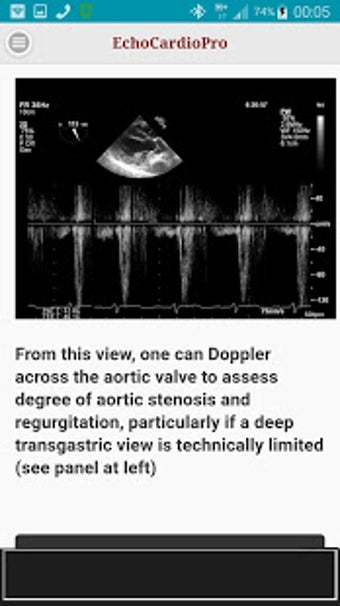

Aplikacja dostarcza kompleksowych informacji na temat echokardiografii przezklatkowej (TTE) i echokardiografii przełykowej (TEE) oraz ich odpowiednich korzyści w ocenie czynności skurczowej i rozkurczowej lewej i prawej komory, regionalnego ruchu ściany, wad zastawkowych serca i chorób osierdzia. Zawiera również szczegółowe informacje na temat różnych widoków, takich jak długoosiowy przysercowy, krótkoosiowy przysercowy, wierzchołkowy, podżebrowy, nadobojczykowy, śródprzełykowy, poprzezżołądkowy, głęboko poprzezżołądkowy i wysoko przełykowy.